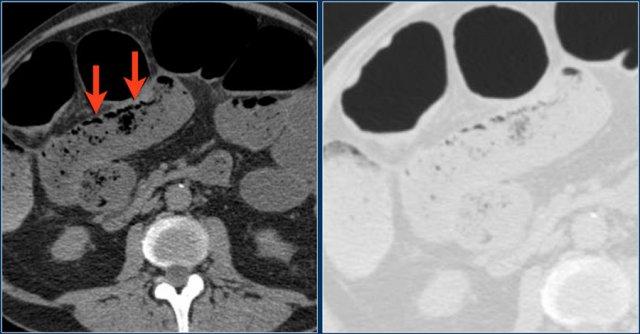

Các hình ảnh này thuộc về bệnh nhân bị tắc ruột non dạng quai kín.

Lưu ý nhóm các quai ruột non có thành dày ở vùng bụng trên phải (mũi tên vàng).

Phù nề mạc treo ruột (mũi tên đỏ) cho thấy tình trạng tăng áp lực tĩnh mạch do thắt nghẹt.

Giãn mạch máu

Tăng áp lực tĩnh mạch trong thắt nghẹt cũng dẫn đến giãn tĩnh mạch (mũi tên vàng).

Bệnh nhân này cũng có tắc ruột dạng quai kín với kiểu ngấm thuốc xám của các quai ruột bị thắt nghẹt (mũi tên đỏ).

Lưu ý sự ngấm thuốc bình thường của ruột non ở phía trên vị trí tắc nghẽn (mũi tên xanh lá).